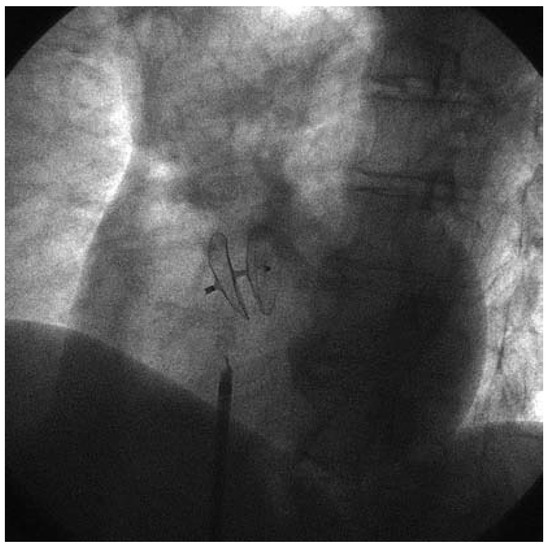

Beneficial Effect of PFO Closure with the Intrasept Device on the Incidence of Migraine Headache

by Carlo Gonnella, Jean-Christophe Stauffer, Manon Siegenthaler, François Perret, Reza Owlya, Milos Savcic, Philippe Beuret, Régis Ménétrey and Jean-Jacques Goy

Cardiovasc. Med. 2007, 10(7), 232; https://doi.org/10.4414/cvm.2007.01256 - 24 Aug 2007

Patent foramen ovale (PFO) may be involved in the development of migraine in some patients. We evaluated the possible beneficial role of PFO closure in patients referred to our institution for this closure. All patients completed the international headache questionnaire to determine migraine [...] Read more.

Patent foramen ovale (PFO) may be involved in the development of migraine in some patients. We evaluated the possible beneficial role of PFO closure in patients referred to our institution for this closure. All patients completed the international headache questionnaire to determine migraine status before treatment and again at 6 months and 1 year after PFO closure. Before intervention, each patient was evaluated clinically by transthoracic and transoesophageal echocardiography. Closure of PFO was attempted in 123 patients (58 men and 65 women) with a mean age of 51 ± 10 years. Twentyeight of these patients (16%) (16 women and 12 men) had true migraine attacks prior to intervention. All patients were treated medically with anti-inflammatory drugs or triptan derivates before intervention. At 6 month the PFO was completely closed at rest in 94% of patients. A small (grade 2) residual shunt was present during Valsalva in 14% of patients. All patients received antiplatelet therapy (acetylsalicylic acid [ASA] and clopidogrel) for 6 months. Among the 28 patients with migraine, 10 patients (37%) were completely free of migraine and another 10 patients (37%) reported a significant improvement in their symptoms with less attacks, less pain and were taking less medication. Five patients (19%) had no change and 1 patient (7%) had a significant worsening of his symptoms. Finally 1 patient (1%) without migraine before the intervention started to have migraine attacks during follow- up. Four patients with migraine had residual shunt of which two were improved and 2 had no changes in their symptoms. Our data confirmed a possible positive effect of PFO closure in the prevention and treatment of migraine. Full article